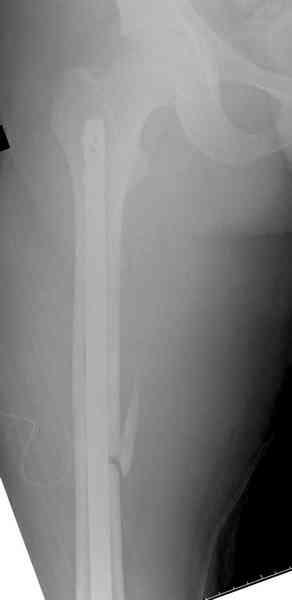

Предыдущей сменой до 4:00 утра по поводу открытого перелома бедра, тибиал плато, пилон и надколенника сделана операция.

Пострадавшему 21 г., травма скоростная, после I&D с расширением раны, на бедре сделана операция ретроградным интрамедуллярным штифтом, остеосинтез с частичной резекцией надколенника и ушивание собственной связки.

На голень наружный фиксатор, рану на бедре ушили (рана была изнутри кнаружи всего 2 см). По протоколу травматических больных, до операции обследован ангиографически, (у больного дистально не смогли определить пульсацию) сосудистый хирург подтвердил проходимость на всем протяжении магистрального сосуда нижней конечности по снимкам ангиограмм.

КТ пилона имеем.